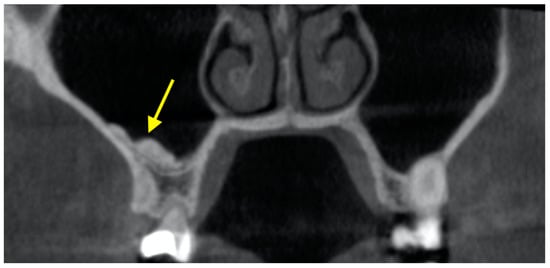

2.1. Posterior Superior Alveolar Artery (PSAA) and Lateral Wall Thickness